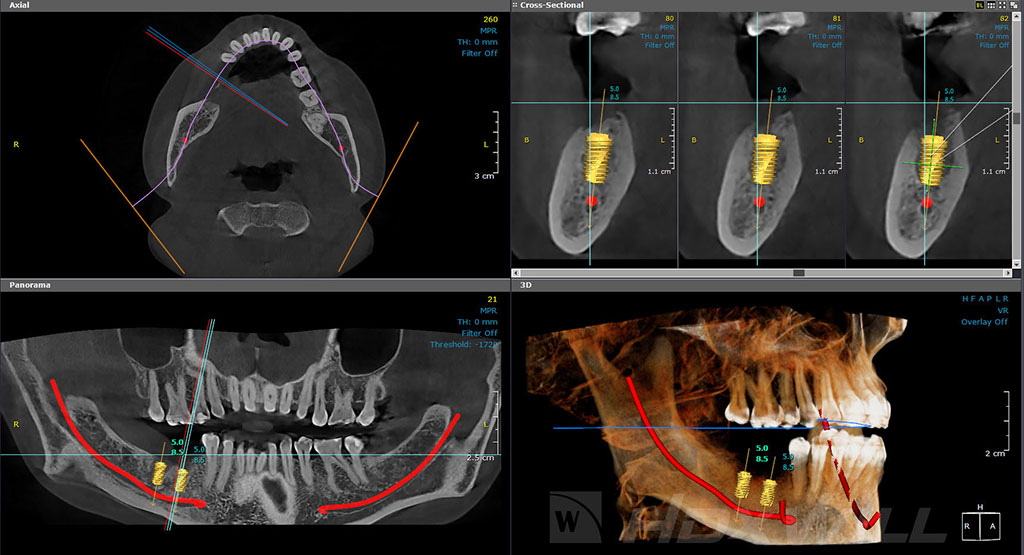

We design a personalized treatment for each patient, in which a specific type of implant is selected. It is always necessary to perform radiological evaluations to determine the quality and quantity of existing maxillary bone in each patient. Bone grafting or other procedures may be required to ensure the success of the implant.

We have excellent surgical and bone regeneration techniques to promote the formation and growth of new compact bone in the maxilla, which will allow the osseointegration of the implant for guaranteed success.